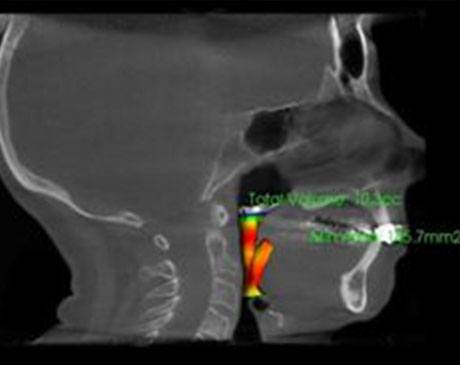

Snoring is the number one sign of sleep apnea. Sleep apnea is a condition where there are breaks or pauses in your breathing while you sleep. It is caused by the soft tissues in your palate or throat relaxing into your airways when you sleep, as well as the general narrowness of the airways and other similar abnormalities. Obstructions are often caused by the soft palate relaxing and descending into the throat during sleep. They are also common in people who are overweight or who have a short or thick throat. Oversized tonsils and adenoids can also cause the obstruction. In many cases, the obstruction is not visible when looking into the patient’s mouth or by feeling their throat, so the detailed images provided by Dr. Shokri and her 3D imaging technology are much more effective at identifying any obstructions to diagnose sleep apnea and determine the best course of treatment.Other signs of the condition include daytime tiredness, weight-gain, difficulty concentrating, and moodiness.

Dr. Shokri is unique in her holistic approach to dental healthcare. Her use of state of the art technology like the Galileo 3D scanner allows her to identify the root cause of the obstructive sleep apnea and provide the most effective in-office or at home treatment available. If you snore, wake often during the night, suffer from daytime drowsiness, weight gain, or moodiness, seek an assessment. The health risks associated with sleep apnea are serious but avoidable with proper treatment.